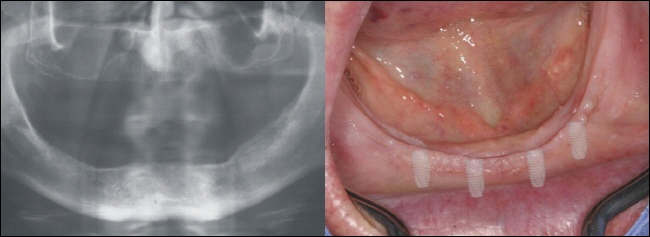

![]() |